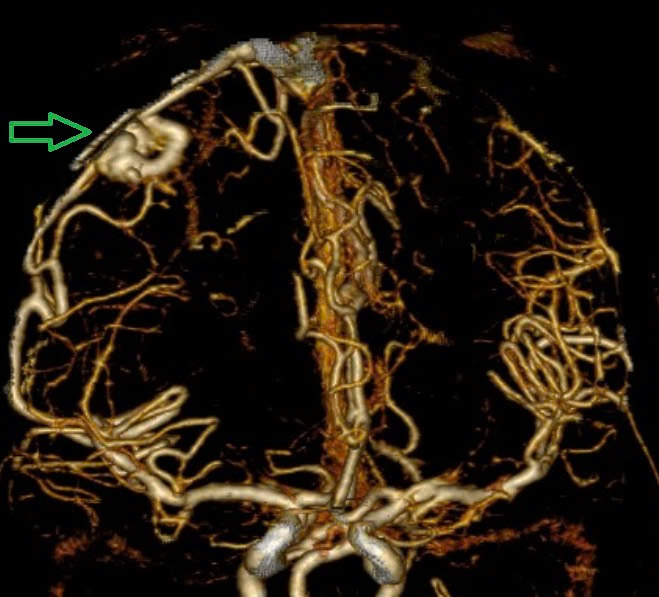

Chụp MSCT mạch não cho thấy chảy máu não thuỳ đỉnh phải, chảy máu não thất do vỡ AVM ( điểm Spetzler Martin 2 điểm). Bệnh nhân đã được phẫu thuật lấy máu tụ và khối dị dạng. Tuy được điều trị tích cực nhưng di chứng để lại vô cùng nặng nề.

Hình ảnh chụp MSCT mạch não: Chảy máu não thuỳ đỉnh phải, chảy máu não thất do vỡ AVM ( điểm Spetzler Martin 2 điểm) bệnh nhân nữ, 29 tuổi. Ảnh BVCC